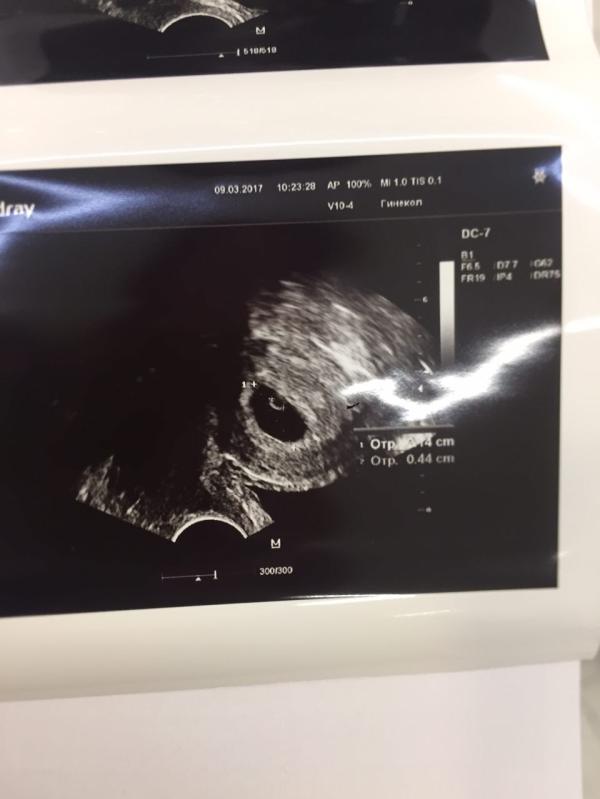

А у нас сегодня состоялась первая встреча с нашим чудом! Небольшой чёрненький комочек на УЗИ вызвал столько эмоций, я аж прослезилась! Мы так долго этого ждали, через столько прошли и наконец дождались! Теперь жду не дождусь следующей встречи😀